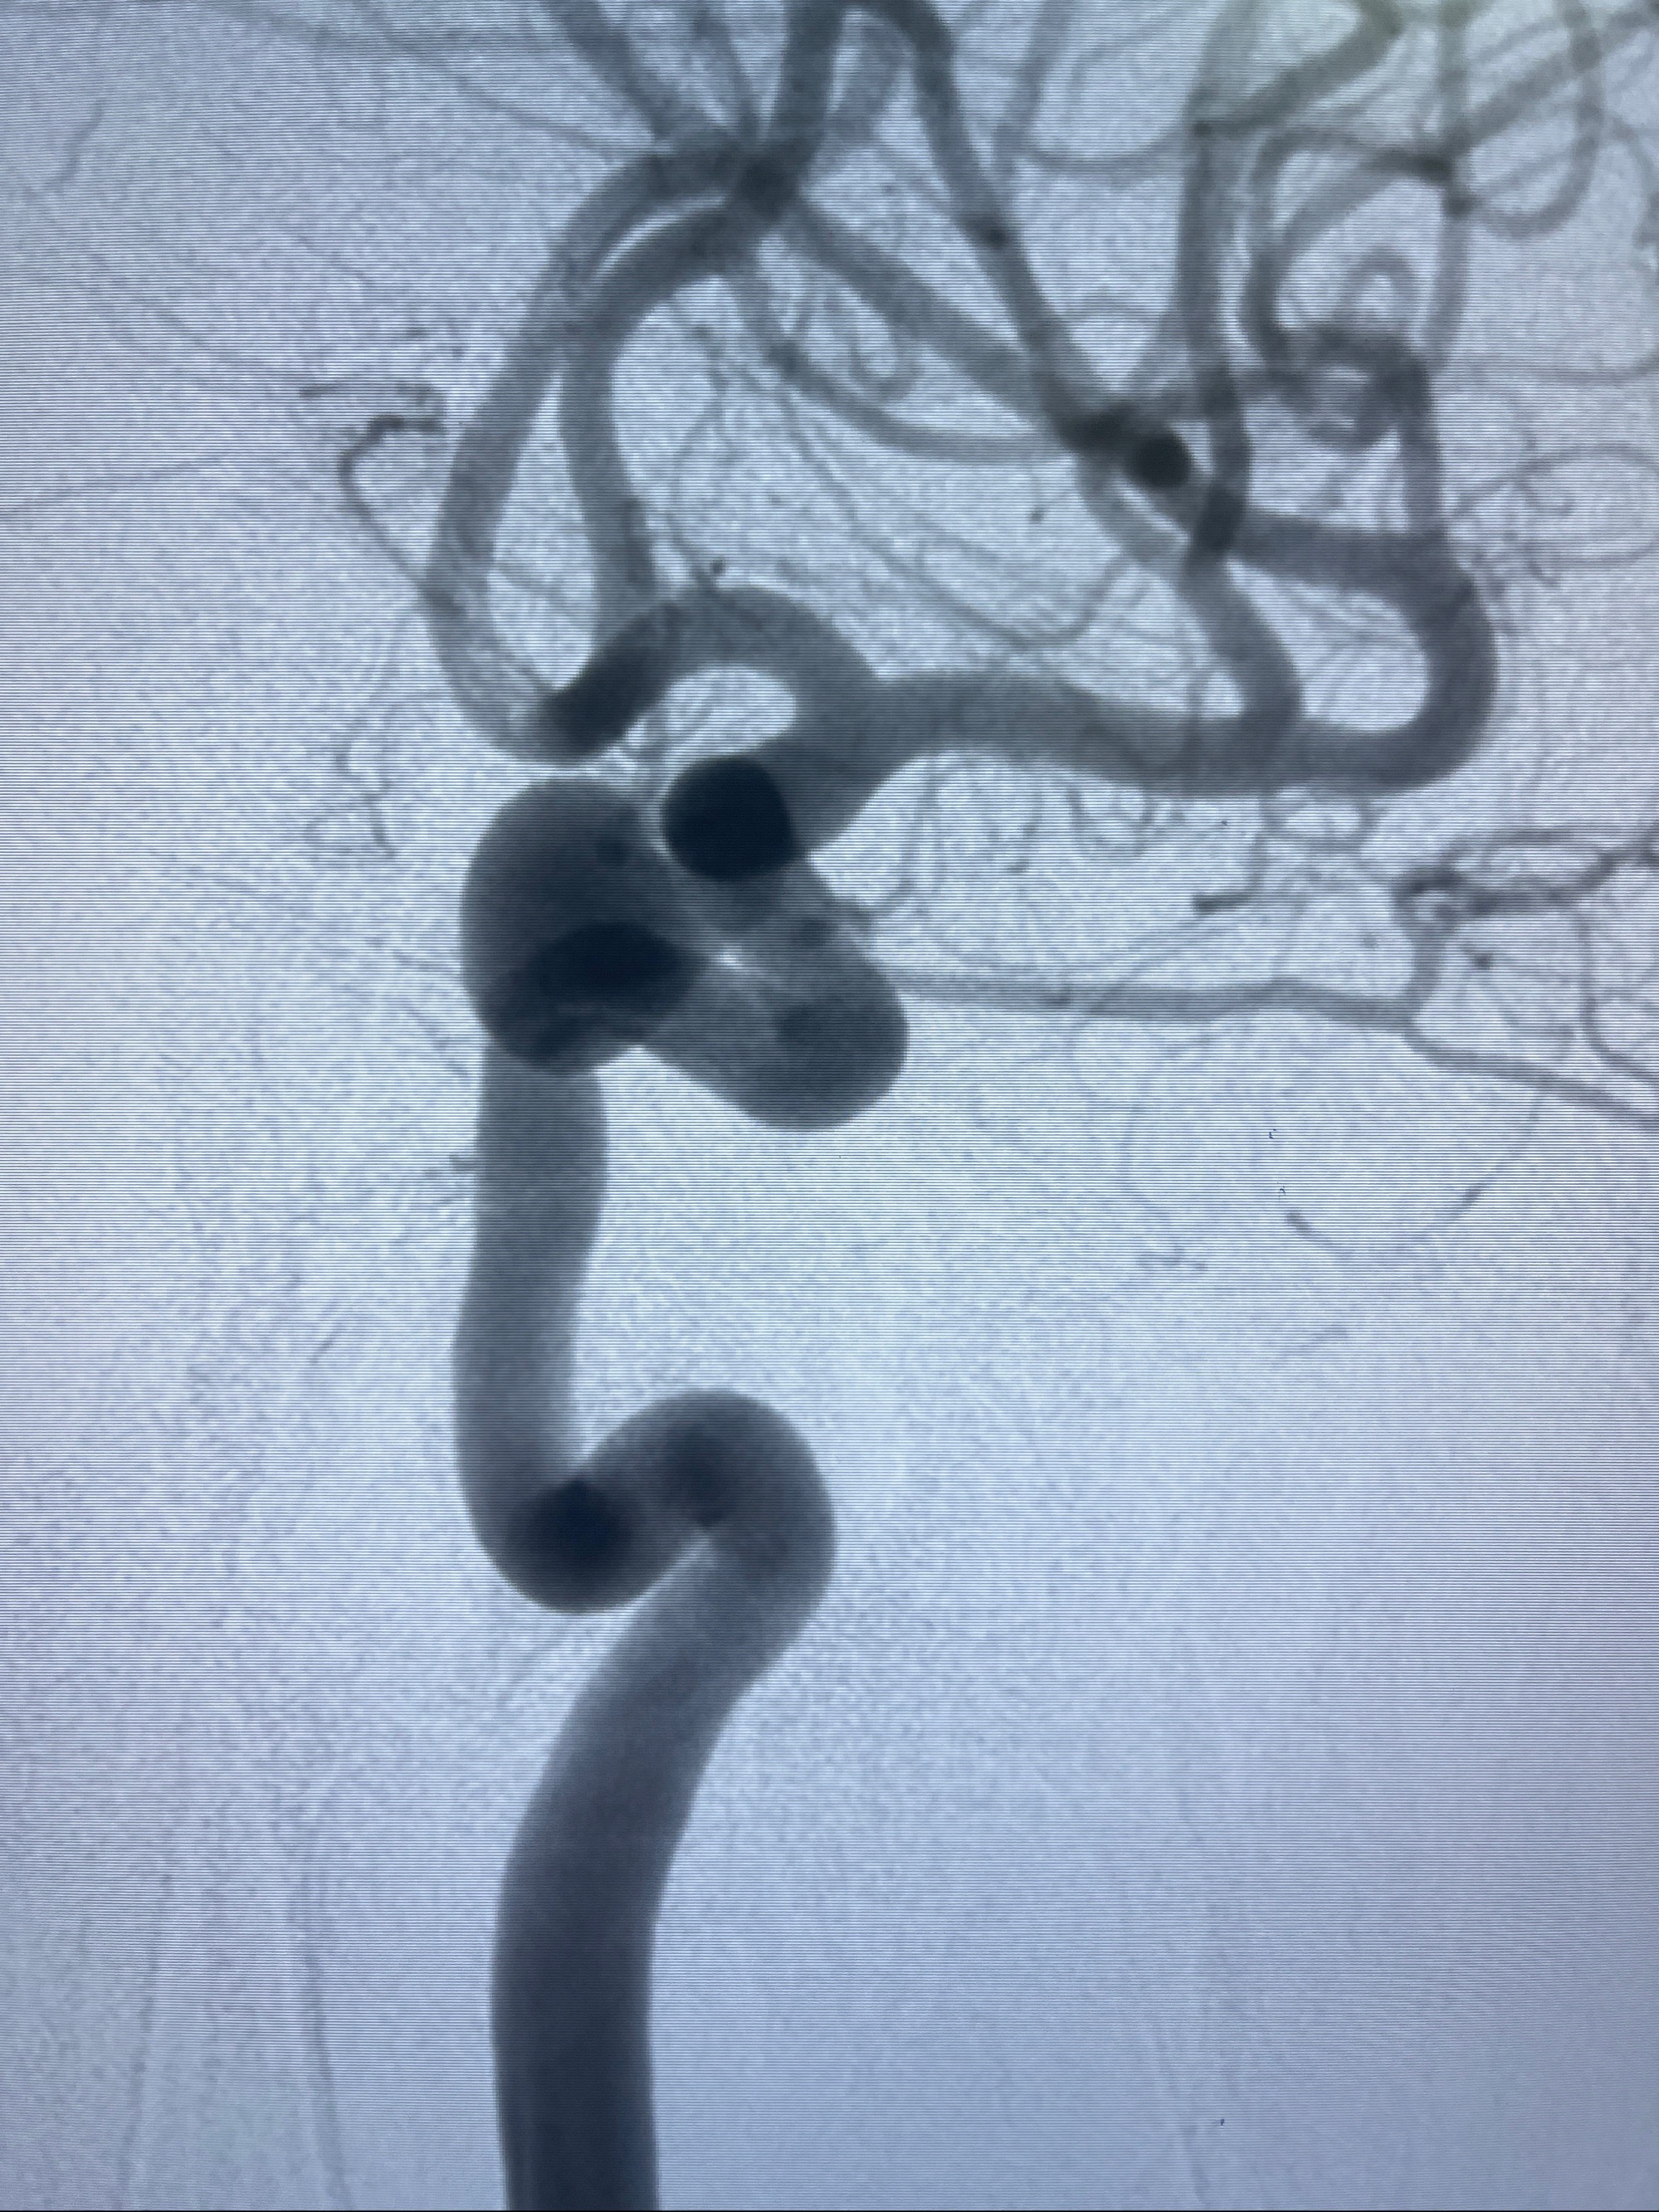

2023-08-30DSA:左侧颈内动脉眼动脉动脉瘤,约3*9.2*7.3mm大小

1.左侧颈内动脉眼动脉段动脉瘤

2023-09-06全麻下行左侧颈眼动脉瘤

密网支架辅助栓塞

术后3D显示支架贴壁佳